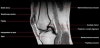

무릎 관절의 MRI 단면영상2016-08-31카테고리 106원본 보기1. Sagittal section 2. Coronal section 3. Axial section ← 이전 글전방 족근관증후군(Anterior tarsal tunnel syndrome) : 발등이 꽉 끼는 구두를 신은 후부터 발등을 누르면 아프고 엄지와 검지 발가락 사이가 저려요다음 글 →흉곽출구증후군(Thoracic outlet syndrome) : 팔이 아프고 감각이 떨어지면서 저려요같은 카테고리 글2017-06-10톰슨 검사(Thompson test) : 아킬레스건 파열을 조사하는 테스트2017-06-09Apley 압박 검사(Apley compression test) : 반월상 연골 손상을 조사하는 테스트2017-06-08맥머레이 시험(McMurray test) : 반월상 연골 손상을 조사하는 테스트← 전체 글로 돌아가기